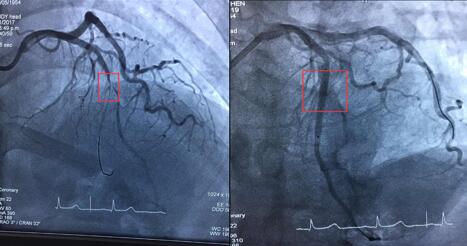

术前术后对比图

9日下午,在手术过程中,毛主任发现范阿姨的血管比当初检查时还要严重,其前降支已经100%是堵塞了,这给手术增加了不少难度。原本植入一枚支架只需要30分钟左后的时间,而范阿姨的整台手术却花了将近2个小时。手术中,毛主任用尽各种方法,使用特殊导丝、微导管等方法对闭塞的血管进行逐步开通,通过血管腔,再用球囊扩开,最后放入支架。一旁,德籍心内科专家Strasser 博士也在现场进行手术指导,为患者提供双重保障。

据介绍,该手术的难点在于患者血管全部堵塞,导丝难以通过血管,导致手术难度大,这需要医生的耐力和患者的积极配合。据统计,在国内,这样的手术有超过一半以上会被迫放弃。值得一提的是,在范阿姨的手术中,尽管困难不断,但是患者始终积极配合医生,充分相信医生的医术,同时毛主任及其手术团队用耐心、用实力成功打开完成堵塞的血管,成功放入一枚药物涂层支架。